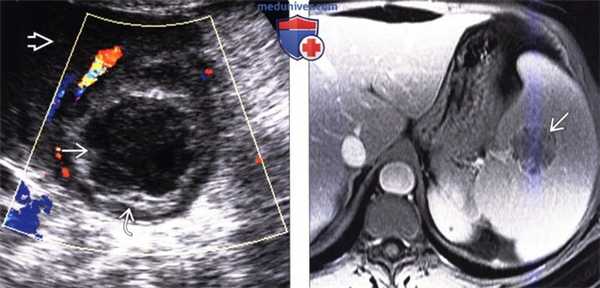

(Справа) На аксиальной КТ с контрастным усилением у пациента с недавней травмой селезенки, у которого возник новый виток лихорадки, определяется скопление жидкости (уровень «жидкость-газ») окруженное «ободком», накапливающим контрастное вещество (абсцесс селезенки). Было выполнено чрескожное дренирование абсцесса, пациенту назначены антибиотики. (Слева) На аксиальной КТ с контрастным усилением у пациента со СПИД, обусловленным ВИЧ, с жалобами на снижение веса тела и лихорадку, визуализируются микроабсцессы по всей селезенке. Состояние пациента быстро ухудшилось, и он погиб; при вскрытии были обнаружены множественные туберкулезные абсцессы.

(Слева) На цветовой допплерограмме визуализируется единичный абсцесс селезенки с четкими контурами, гипоэхогенной центральной частью (некроз) и неравномерно утолщенной стенкой. Прилежащие к абсцессу участки паренхимы селезенки не выглядят патологически измененными. Обратите внимание на типичный а васкулярный характер абсцесса.

(Справа) На аксиальной Т1 МР томограмме с контрастным усилением у пациента с жалобами на боль в верхних отделах живота слева и повышение температуры тела определяется абсцесс селезенки с наличием множественных перегородок в структуре. При культуральном исследовании крови был выявлен стафилококк, пациент выздоровел на фоне приема антибиотиков.